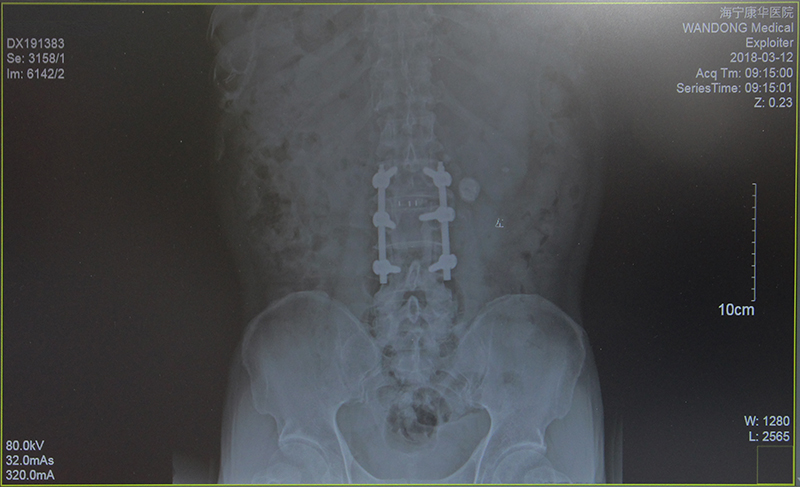

“大伯恢复得不错啊。”眼看沈大伯能流畅地自己行走,鲍立峰十分欣慰,“来,您先坐这里,我再看看您这次的片子。”调出电脑中前后两次的拍片记录,鲍立峰向沈先生解释大伯最新的骨骼状况,“钢钉位置挺好的,骨头正在慢慢长起来了。”

经过详细的术前检查与计划,2月2日,在鲍立峰主刀下,为沈大伯进行了“腰2/3,腰3/4减压术及腰2/3椎体融合术”。整台手术历时约3小时,较好地纠正了大伯多处突出的腰椎。第二天,沈大伯的左下肢已经恢复了肌力。随后,配合康复治疗等,两周后,大伯顺利出院了,此时的他已经基本可以靠着拐杖独立行走了。

(术前)

(术后)